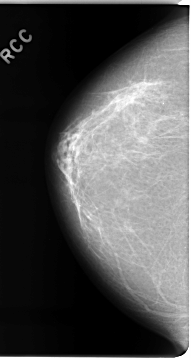

C_0075_1.RIGHT_CC

DATE_OF_STUDY 10 1 1994

PATIENT_AGE 51

FILM_TYPE REGULAR

DENSITY 2

RIGHT_CC LINES 4648 PIXELS_PER_LINE 2472 BITS_PER_PIXEL 12 RESOLUTION 50 NON_OVERLAY